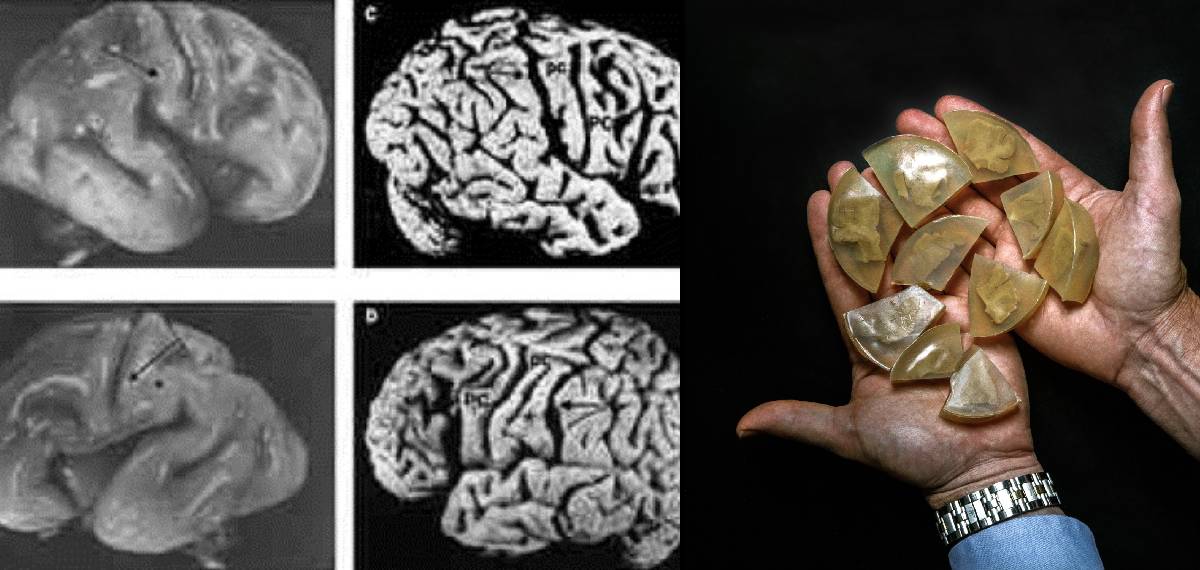

ഐന്സ്റ്റീന്റെ തലച്ചോറ് ലഭിച്ചതിന് പിന്നാലെ ഹാര്വിക്ക് പ്രിന്സ്റ്റണ് ആശുപത്രിയിലെ ജോലി നഷ്ടപ്പെട്ടു. പക്ഷേ ഡോ. ഹാര്വി തലച്ചോറില് ഗവേഷണം നടത്താന് തീരുമാനിച്ചിരുന്നു. ഐന്സ്റ്റീന്റെ തലച്ചോറുമായി ഹാര്വി ഫിലാഡല്ഫിയയിലേക്കും കാന്സസും മിസോറിയും ഉള്പ്പെടെയുള്ള മിഡ് വെസ്റ്റ് രാജ്യങ്ങളിലേക്കും യാത്ര ചെയ്തു. ഡോ. ഹാര്വി തലച്ചോറിന്റെ ഭാഗങ്ങള് 240 കഷണങ്ങളായി മുറിക്കുകയും കഷണങ്ങള് ജാറുകളില് സൂക്ഷിക്കുകയും ചെയ്തു. 12 സെറ്റ് മൈക്രോസ്കോപ്പിക് സ്ളൈഡുകളും സൃഷ്ടിച്ചു. ചില സാമ്പിളുകള് ശാസ്ത്രജ്ഞന്മാക്ക് പഠിക്കാനായി നല്കിയിരുന്നു. തന്റെ ജോലി ആവശ്യങ്ങള്ക്കായി ഡോ. ഹാര്വി പല സ്ഥലങ്ങളില് സഞ്ചരിക്കുമ്പോഴും ഐന്സ്റ്റീന്റെ തലച്ചോറും കൊണ്ടുപോകുമായിരുന്നു. ലബോറട്ടറി ജാറുകള് മുതല് ബിയര് കൂളര് വരെയുള്ള പാത്രങ്ങളിലാണ് തലച്ചോര് സൂക്ഷിച്ചിരുന്നതെന്ന് പറയപ്പെടുന്നു.

ഐന്സ്റ്റീന്റെ തലച്ചോറിനെ അടിസ്ഥാനമാക്കിയുള്ള ആദ്യത്തെ പഠനം അദ്ദേഹത്തിന്റെ മരണത്തിന് മൂന്ന് പതിറ്റാണ്ടുകള്ക്ക് ശേഷം 1985ലാണ് പുറത്തുവന്നത്. ന്യൂറോ സയന്റിസ്റ്റ് മരിയന് ഡയമണ്ടിന്റെ നേതൃത്വത്തില് തലച്ചോറിലെ കോര്ട്ടക്സിന്റെ ഭാഗങ്ങളില് പഠനങ്ങള് നടത്തുകയും കോശങ്ങള് മെച്ചപ്പെട്ട വൈജ്ഞാനിക ശേഷിയുമായി ബന്ധപ്പെട്ടിരിക്കുന്നുവെന്ന് കണ്ടെത്തുകയും ചെയ്തു. എന്നാല് ഒരൊറ്റ തലച്ചോറില് മാത്രം നടത്തിയ പഠനത്തിന് ബുദ്ധിശക്തിയെക്കുറിച്ച് അര്ഥവത്തായി അറിവ് നല്കാന് കഴിയില്ലെന്ന് വിമര്ശകര് വാദിച്ചു. നരവംശശാസ്ത്രജ്ഞനായ ഡീന് ഫോക്ക് 2013-ല് നടത്തിയ ഒരു പഠനത്തില് പറയുന്നത് തലച്ചോറിന്റെ ഇടത്, വലത് അര്ദ്ധഗോളങ്ങളെ ബന്ധിപ്പിക്കുന്ന നാരുകളുടെ കൂട്ടമായ കോര്പ്പസ് കാലോസം, ഐന്സ്റ്റീന്റെ തലച്ചോറില് താരതമ്യേന കട്ടിയുള്ളതാണെന്നും, ഇത് കൂടുതല് ഇന്റര്-ഹെമിസ്ഫെറിക് ആശയവിനിമയത്തിന് സഹായിക്കുന്നുവെന്നുമാണ്.

ഈ കാലയളവില് ഐന്സ്റ്റീന്റെ തലച്ചോറിന്റെ ഭാഗങ്ങള് സ്വകാര്യ ഉടമസ്ഥതയില് നിന്ന് പൊതു സ്ഥാപനങ്ങളിലേക്ക് മാറ്റിയിരുന്നു. ഫിലാഡല്ഫിയയിലെ മ്യൂട്ടര് മ്യൂസിയത്തില് 46 ഭാഗങ്ങള് ലഭിച്ചു. കൂടുതല് ഭാഗങ്ങള് നാഷണല് മ്യൂസിയം ഓഫ് ഹെല്ത്ത് ആന്ഡ് മെഡിസിലേക്ക് അയച്ചു. ഐന്സ്റ്റീന്റെ ബുദ്ധിശക്തിയെക്കുറിച്ച് അറിയാനുളള ഹാര്വിയുടെ ആഗ്രഹവുമായി ബന്ധപ്പെട്ട ഒരു പദ്ധതിയും യാഥാര്ത്ഥ്യമായതുമില്ല. ഐന്സ്റ്റീന്റെ ബുദ്ധിക്ക് പുറകിലുള്ള കൃത്യമായ ജീവശാസ്ത്രപരമായ വിശദീകരണമൊന്നും പുറത്തുവന്നുമില്ല.